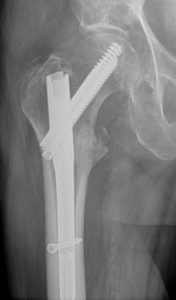

Intertrochanteric fractures are located in the upper end of the thigh bone in the region just below the femoral neck. Although close in proximity to femoral neck fractures, these fractures are very different from each other. One reason for this difference is that the intertrochanteric region of the hip has an excellent blood supply, whereas the blood supply through the femoral neck and into the femoral head (ball) is somewhat more tenuous. The blood supply to a fracture has a direct impact on the ability to heal. Because of this blood supply intertrochanteric fractures are likely to heal with surgical repair. Surgery typically involves re-alignment of the bones and fixation with either a plate and screws construct, or a rod and screws device (Figure 2).